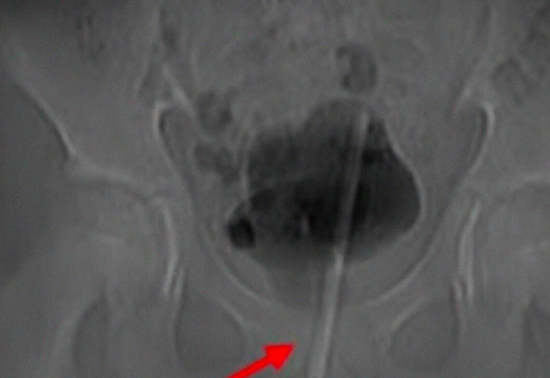

12-летний ребёнок из Китая ввёл термометр в уретру во время мастурбации, и тот вскоре оказался в мочевом пузыре.

Чтобы извлечь предмет, врачи проделали небольшое отверстие в животе и добрались до мочевого пузыря напрямую. Вытягивать его обратно через уретру было бы слишком травмоопасно.